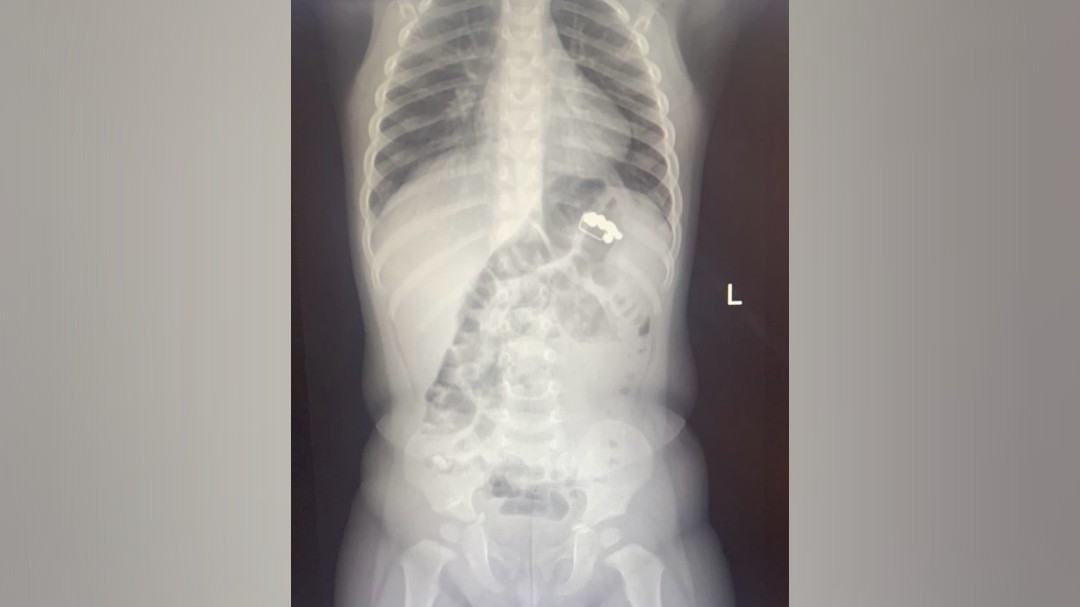

В больнице мальчику сделали рентген органов грудной клетки, который и помог выяснить настоящую причину недомогания – на снимке врачи заметили восемь магнитов и скрепку.

На контрольном рентгеновском снимке врачи заметили в ЖКТ малыша еще два магнита, которые после постановки очистительной клизмы вышли естественным путем. Специалисты считают, что магниты мальчик проглотил в разное время.